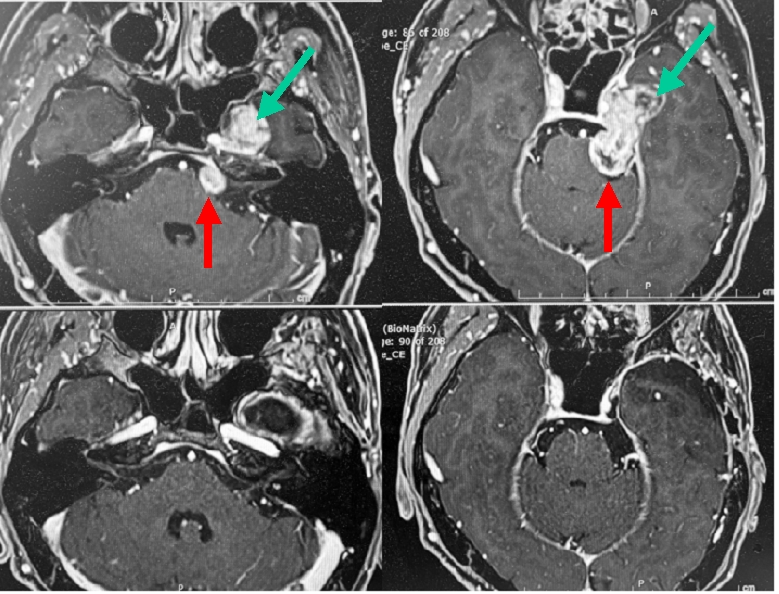

めまい、ふらつきといった小脳症状で発症した小脳血管芽腫です(上断赤矢印)。後頭葉を圧排して小脳テントとよばれる部位を切開して腫瘍に到達し、全摘出しました(中段の写真)。中段写真の緑の矢印は、切開した小脳テント部を示しています。下段は術中所見を示しています。術後は後遺症なく退院できました。この腫瘍は血行に富み、他の良性腫瘍と異なり内減圧という手法がとれないので、一般に摘出難度が高い腫瘍と言えます。